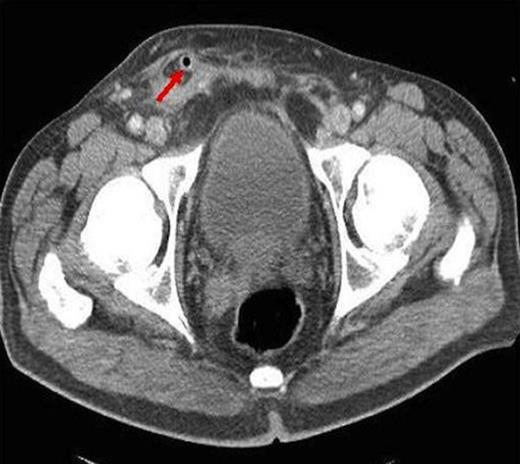

Coronal CT showing descent of appendix segment into scrotum and associated fat stranding

CT has 18 – 97% sensitivity and near 100% specificity and up to 98% accuracy in diagnosing intra-abdominal appendicitis leading to reduction in negative appendicectomies from 22% to 14% and identification of concurrent pathology in 51% in one series (3). The most common CT findings are that of enlarged appendix with surrounding fat stranding (93%) which is similar to our case (4) (Fig. 2). The only other reported pre-operative detection of appendicitis within a hernia was also diagnosed by CT (5). CT is becoming increasingly available without harmfully delaying surgery and can direct surgical approach.

Primary acute appendicitis is thought to be caused by intra-luminal congestion and inflammation. Appendicitis within herniae is thought to be caused by extra luminal constriction by the hernia neck. The mesh provides another aetiological possibility. There is only one report of acute appendicitis related to hernia repair 18 months prior where the inflamed appendix was adherent to peritonealised mesh. The authors’ postulate appendicitis could have been caused by mesh irritation or appendix adherence to mesh with subsequent kinking leading to inflammation, or primary acute appendicitis which adhered to the old mesh site (8). The demarcation of acute appendicitis in the distal segment in this case suggests appendix entrapment as it had passed into the scrotum or adherence to the medial border of the non-peritonealised exposed mesh (Figure 2).